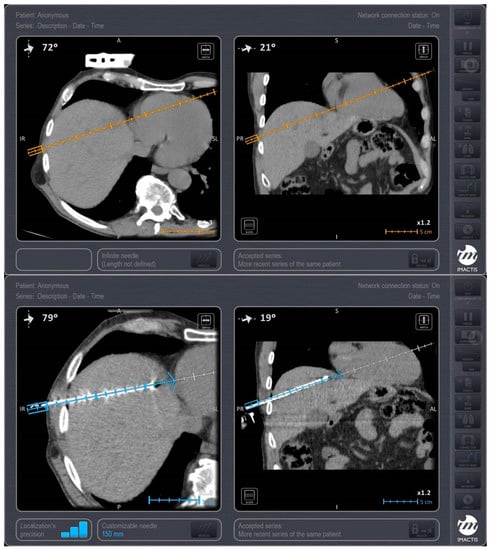

Trajectory planning and insertion of the microwave antenna were conducted using a commercially available navigation system for interventional radiology (IMACTIS SAS, Saint Martin d’Hères, France), (Figure 1). Educating the patient for correct breathing is of outmost importance; in the present study, all scans (both set-up and control ones) as well as needle movements were performed in the end-expiration apnea. In all lesions included in the present study, ablation was performed using a single microwave antenna. Once in the correct location, the ablation session was set up and performed according to the coagulation charts provided by the manufacturer in consideration of the tumor size and location and the desired safety margin. In all sessions, track ablation was performed during antenna removal from the liver in order to reduce potential risk of bleeding and peritoneal tumor seeding. CT scan in the arterial and portal venous phases validated the ablation zone and evaluated any potential immediate complications at the end of the MWA treatment (Figure 2). All patients were hospitalized overnight.

Figure 1. A 65-year-old male patient with colorectal cancer located at left colon with 2 synchronous metastatic lesions at hepatic dome (segment VIII). Stereotactic CT-guided ablation post systemic chemotherapy, and prior to colon resection was performed with the patient in supine position, through the anterolateral approach, under iv analgesia. Upper row: Planning scan for designing the trajectory of approach (orange line) using the IMACTIS CT navigation system. Lower row: Control scan evaluating the antenna’s position in the target lesion using the IMACTIS CT navigation system.